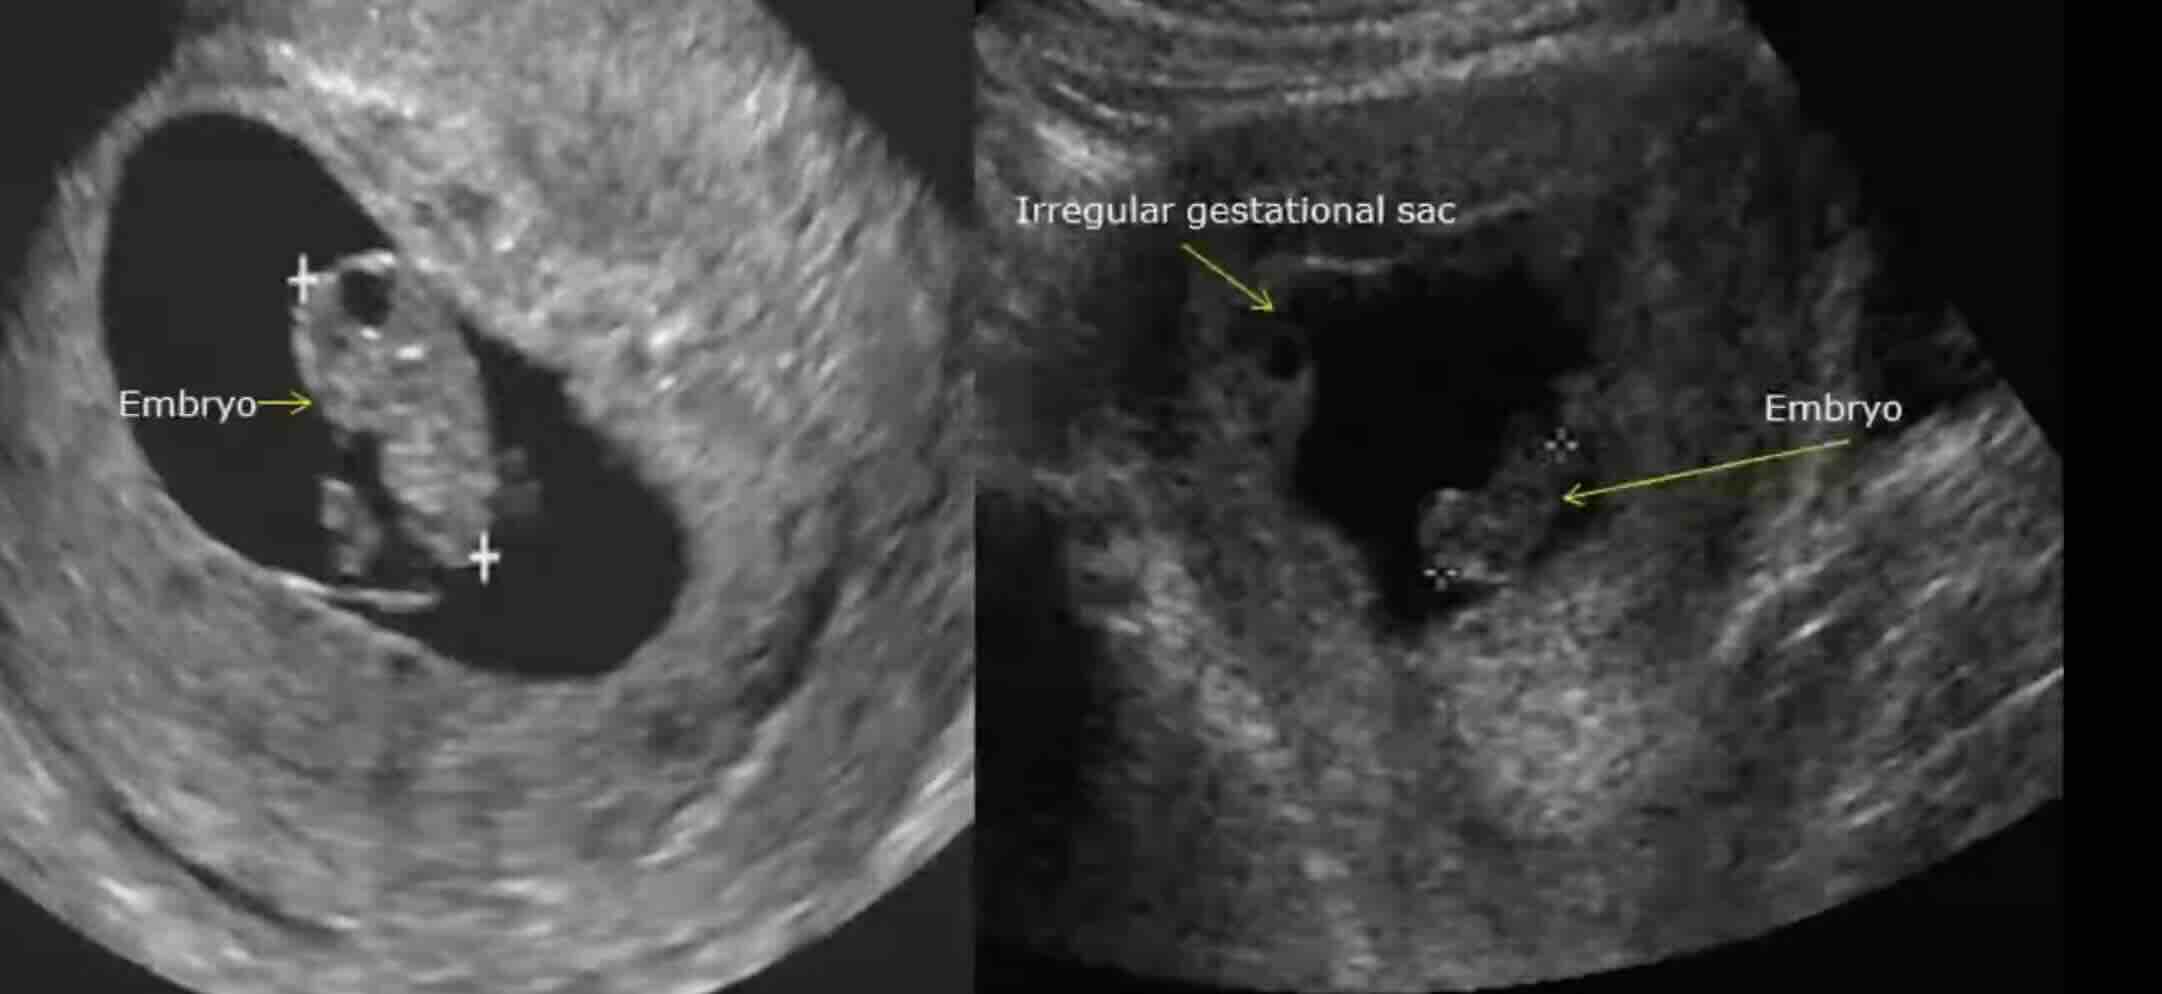

Biyopsi (Servikal Biyopsi):

- CIN'in kesin tanısı için altın standarttır.

- Kolposkopi sırasında saptanan şüpheli alanlardan küçük doku parçalarının alınması işlemidir. Bu parçalar patoloji laboratuvarına gönderilerek mikroskop altında incelenir.

- Patolog, hücrelerdeki anormalliğin derecesini ve epiteldeki yayılımını değerlendirerek CIN 1, CIN 2 veya CIN 3 tanısını koyar. Bazen "CIN saptanamadı" veya "normal servikal doku" sonucu da gelebilir.

- Eğer lezyon rahim ağzı kanalının içine doğru uzanıyorsa veya kolposkopide tam olarak değerlendirilemiyorsa, Endoservikal Küretaj (ECC) adı verilen bir işlemle kanalın içinden de doku örneği alınabilir.